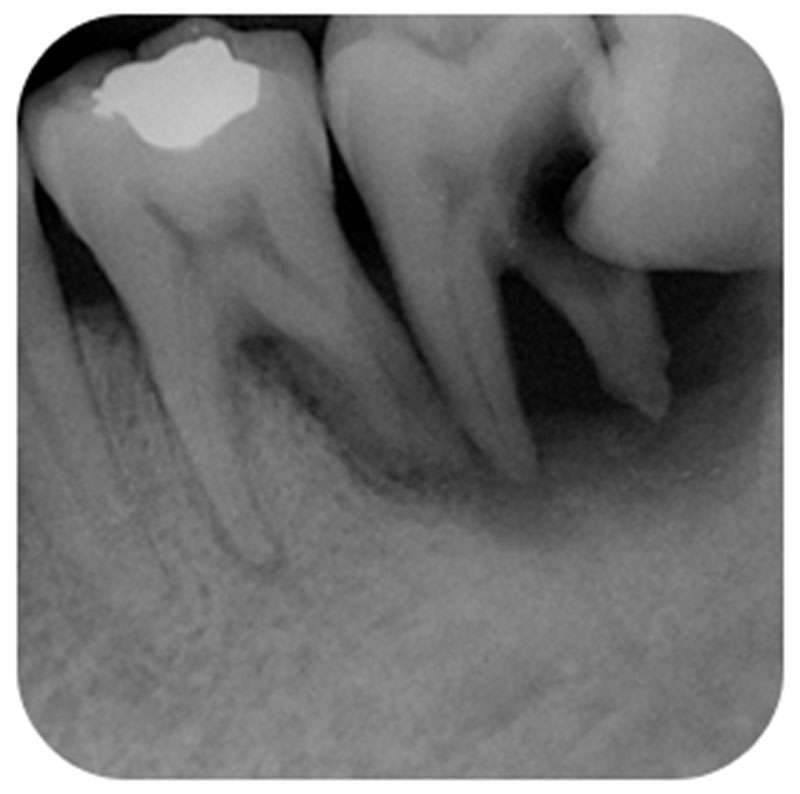

右邊下顎埋在骨頭內的智齒